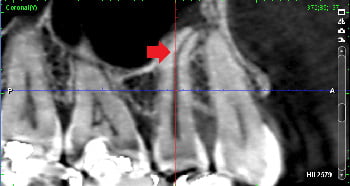

下の画像は、破折ファイルが根管を塞ぎ膿の治療を阻んでいるケースです。CT画像で歯根の先に膿の影がみられますが、破折ファイルが根管を塞いでいるため、このままでは再根管治療によって根管に残る細菌感染を除去し膿を改善することができません。根管治療によって歯を残すために、まさに破折ファイル除去が必要なケースです。(但し、根の周りに膿などの病変がなく根管内に細菌感染が無いことが考えられる場合は、破折ファイルは除去しなくても良いことがあります)